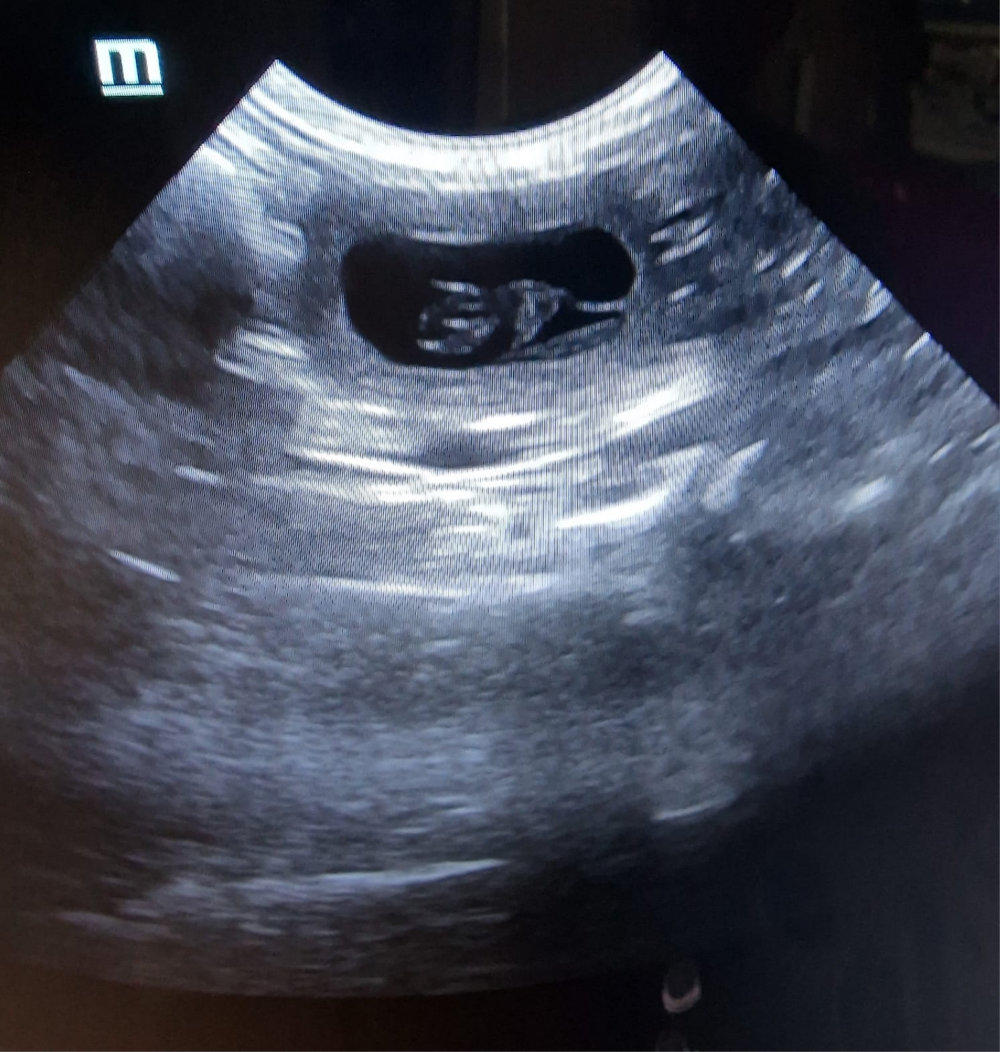

Unser Frauli war mit Enja und Yule „Babys gucken“. Smile.

Enja links. Ein bisschen „Kopfkino“ hat unser Frauli ja schon, denn der Zwerg unten links liegt „mega doof“, um das mal vor- sichtig auszudrücken. So ähnlich war es bei Lotta auch. Jetzt müssen wir alle Daumen und Pfötchen drücken, damit das Baby diese absolut unbequeme Position noch aufgibt und sich richtig hindreht. Ein paar Tage haben wir ja noch.

Bei Yule, logischer- weise rechts, ist alles „chic“!!!